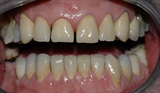

figur IV

Det var her nødvendig å reparere tennene med keramiske kroner.

Slik fikk pasienten tilbake en normal bittfunksjon, og et penere tannsett.